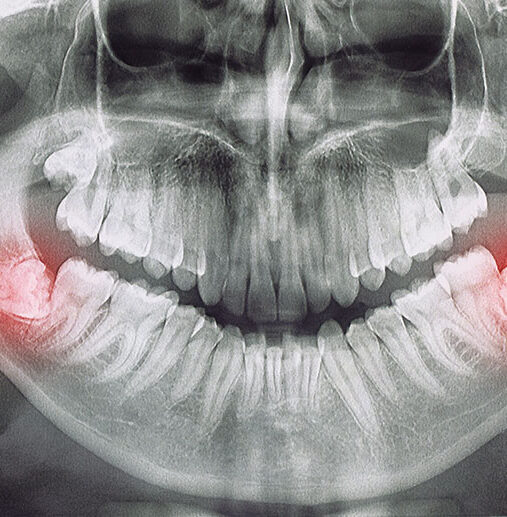

20 Yaş/Gömülü Diş Çekimi

20 Yaş / Gömülü Diş Çekimi Çene gelişimlerinin yeterli olmadığı veya ağız içerisindeki